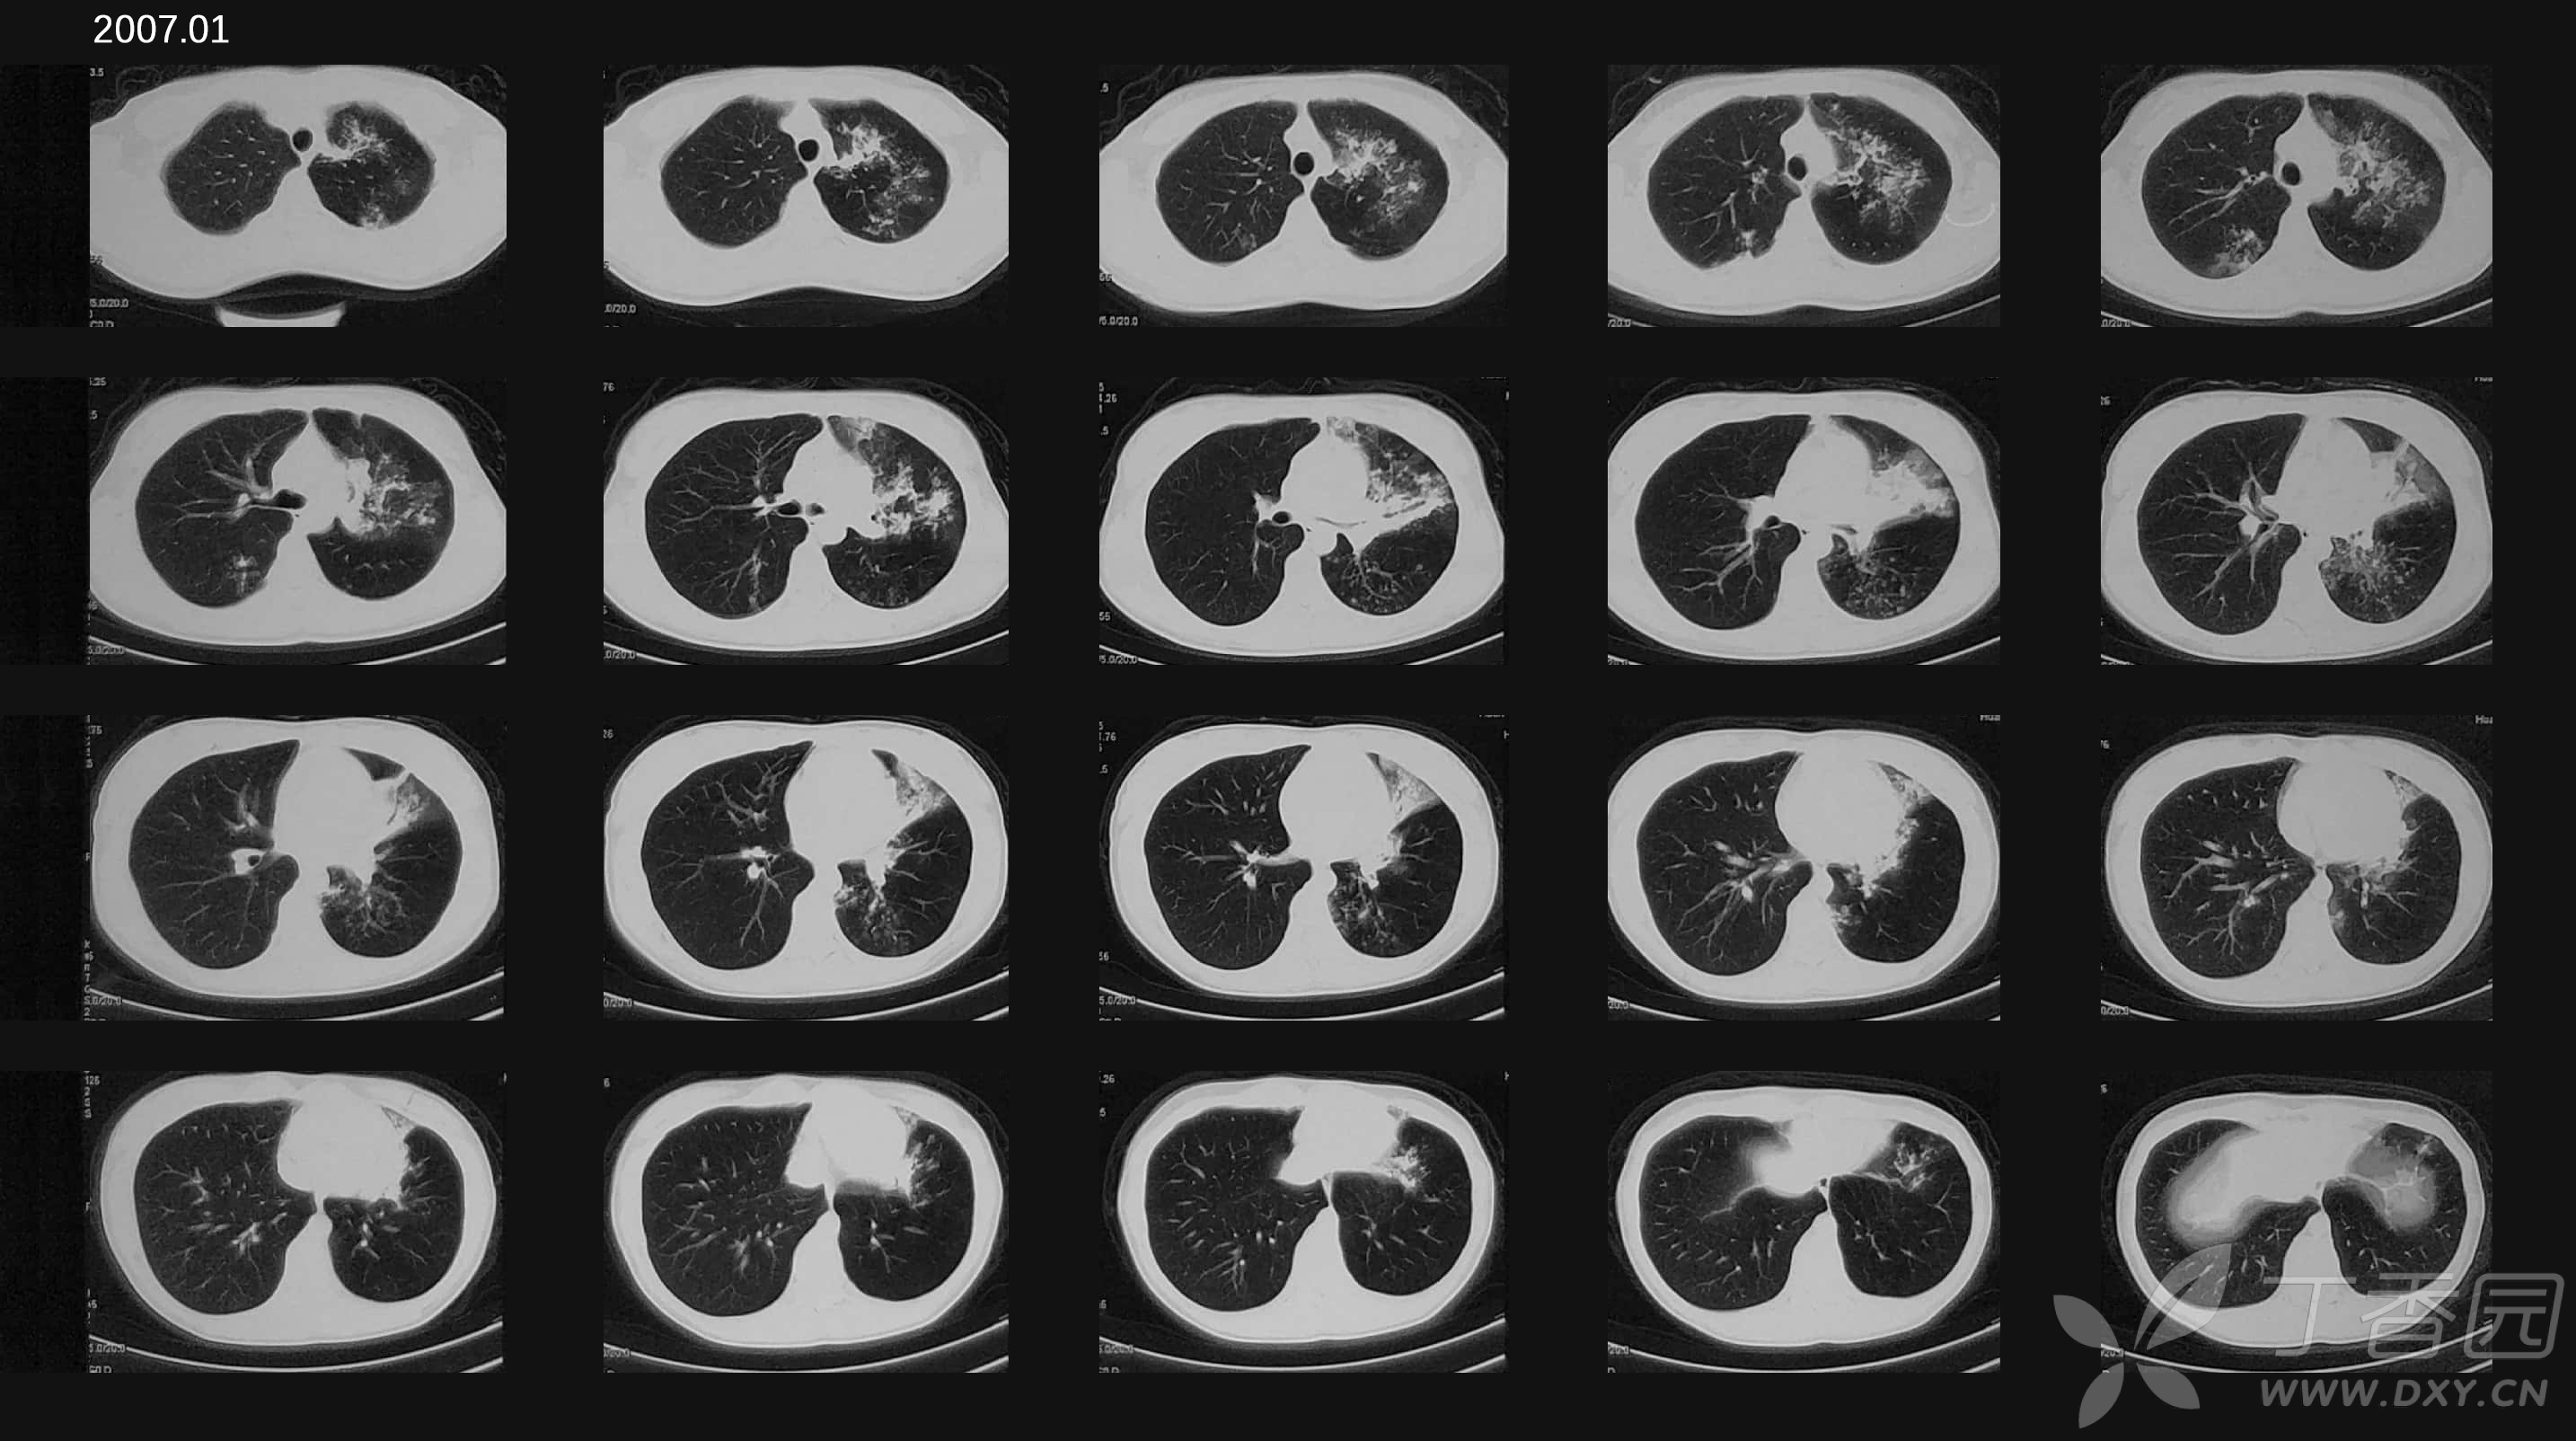

【病例讨论】咯血,ct肺出血:多家医院诊断未明,下一步如何检查和处理

图片尺寸640x741